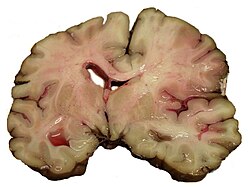

Der ischämische Schlaganfall oder Hirninfarkt (veraltet „weißer Schlaganfall“) ist eine neurologische Erkrankung durch plötzliche Minderdurchblutung und daraus folgende Minderversorgung des Gehirngewebes. Die Minderdurchblutung wird meist durch Einengung oder Verschluss einer oder mehrerer hirnversorgender Arterien verursacht. Selten sind Venenverschlüsse die Ursache. Der ischämische Schlaganfall ist die häufigste Form des Schlaganfalls.

Unterschreitet der zerebrale Blutfluss bzw. die Energiezufuhr die so genannte Funktionsschwelle, stellen die Hirnzellen ihre aktive Funktion zunächst reversibel ein. Es kommt zur Ischämie. Dieser Zustand kann jedoch nur eine bestimmte Zeit aufrechterhalten werden. Bei länger anhaltender Ischämie entsteht ein Infarkt, da die Zellstruktur nicht länger erhalten werden kann. Sinkt der zerebrale Blutfluss bzw. die Energiezufuhr weiter und unter die so genannte Infarktschwelle, werden die Hirnzellen ebenfalls irreversibel geschädigt und sterben ab, so dass ein Infarkt entsteht.

- Ein primär ischämischer Infarkt kann sekundär einbluten. Dies zeigt sich klinisch meist als Zweitereignis. In einem solchen Fall geht man therapeutisch wie bei einer intrazerebralen Blutung vor.